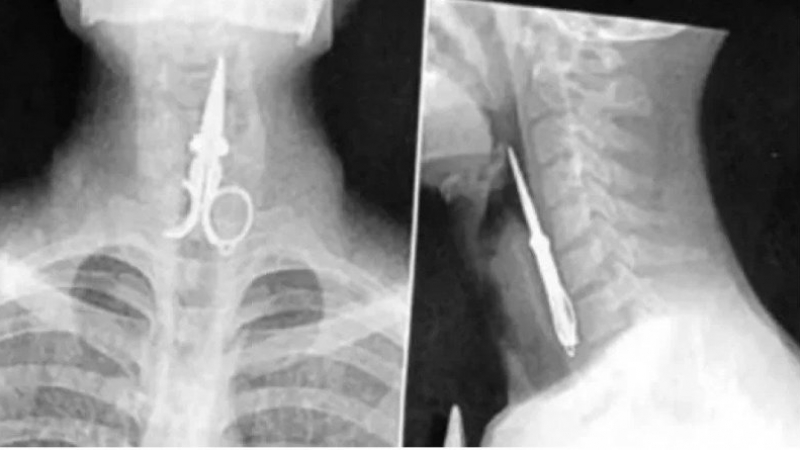

Un preso se tragó una tijera en San Juan y tuvieron que internarlo de urgencia